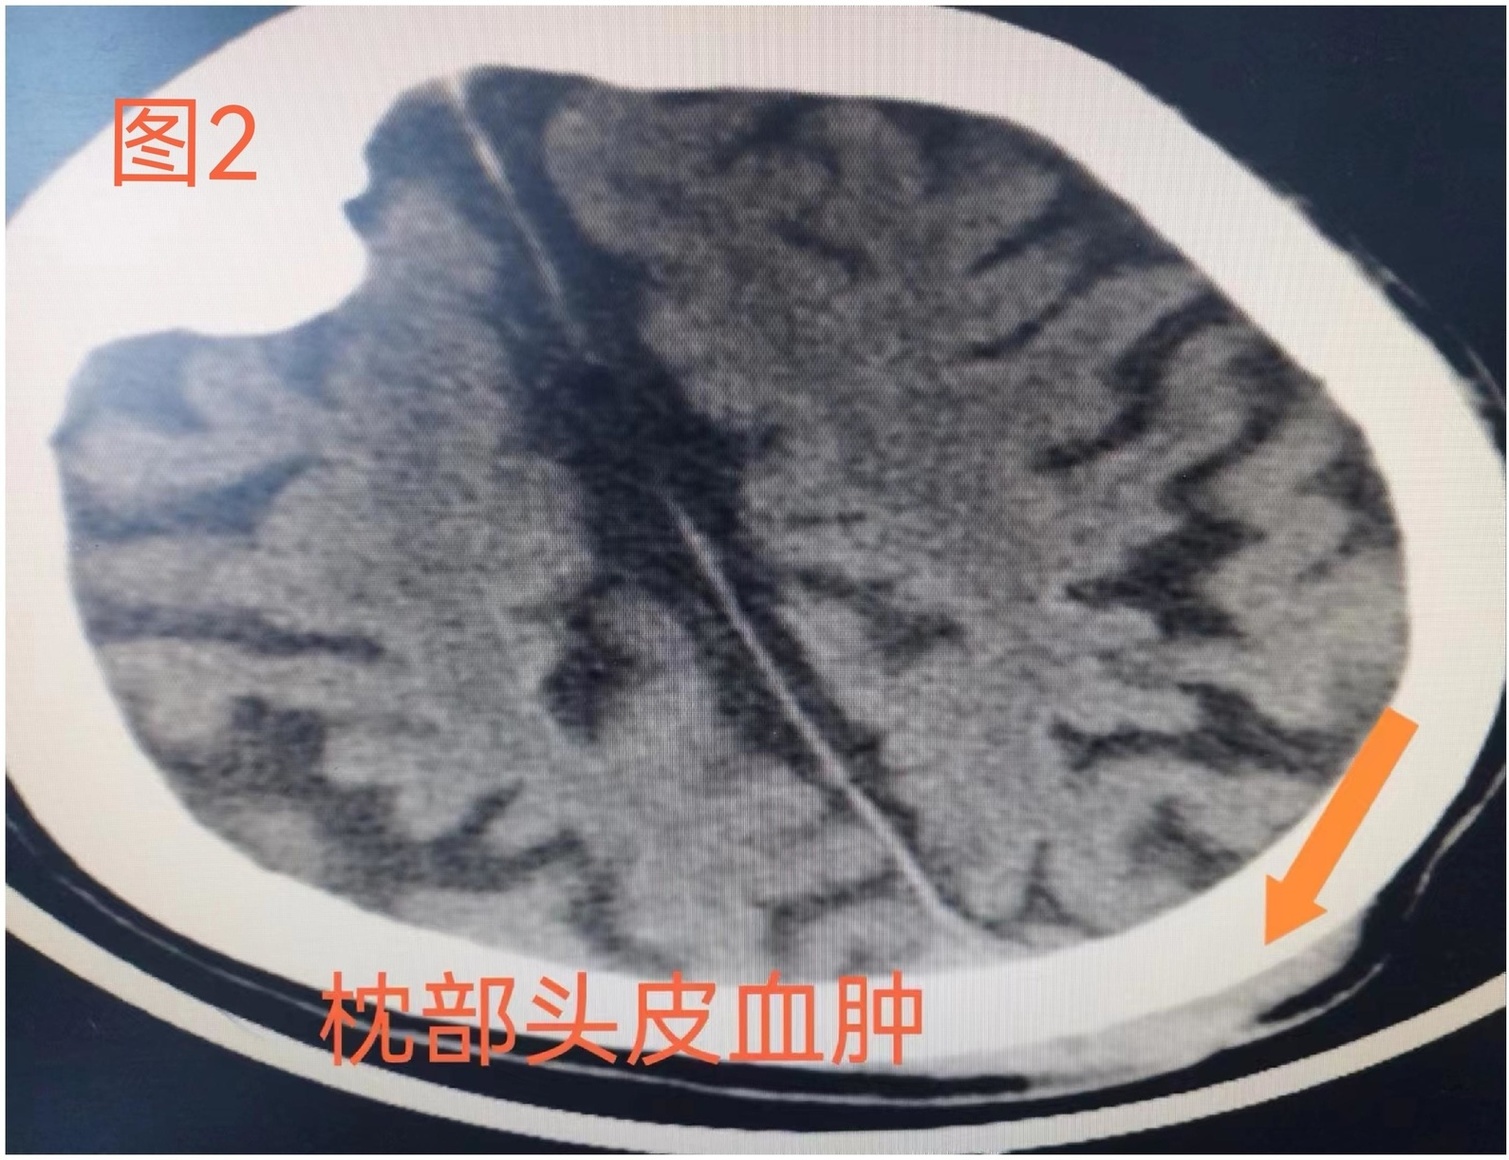

到達(dá)急診科后,患者大汗淋漓,仍處于嗜睡狀態(tài),查體發(fā)現(xiàn)后枕部有一頭皮血腫。急診科王澤鑫醫(yī)生迅速進(jìn)行相關(guān)檢查,做出診斷:1.急性下壁、右室心肌梗死;2.III度房室傳導(dǎo)阻滯、交界性逸搏心律;3. 心源性暈厥;4. 外傷性頭皮血腫,給予“抗栓、穩(wěn)定生命征”等處理。